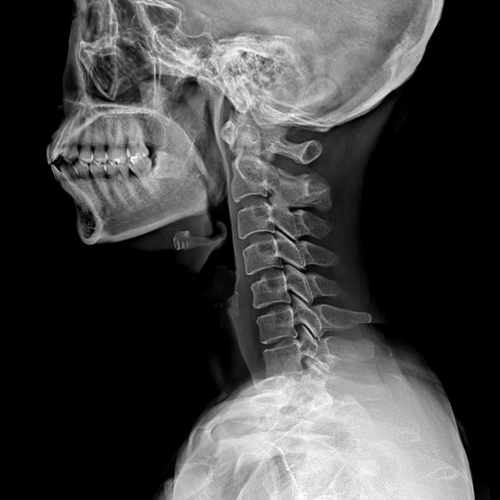

목디스크는 의사의 진찰 소견이 중요합니다.

단순 방사선 촬영은 목 디스크를 보다 강력하게 의심하는 방법은 되지만 확진은 어렵습니다.

근전도 검사가 의료 보험 적용이 되는 디스크 확진 방법이며, MRI는 영상으로 목 디스크가 뒤로 밀린 것을 확인할 수 있습니다.